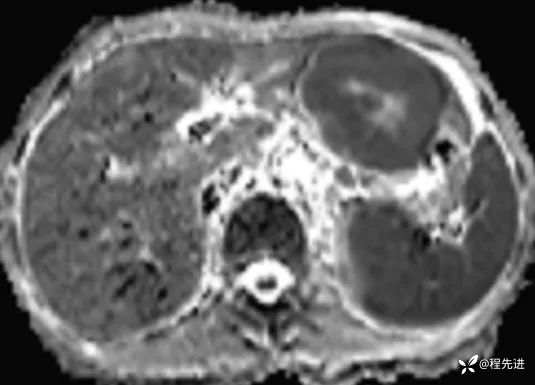

T1及T1增强4期: